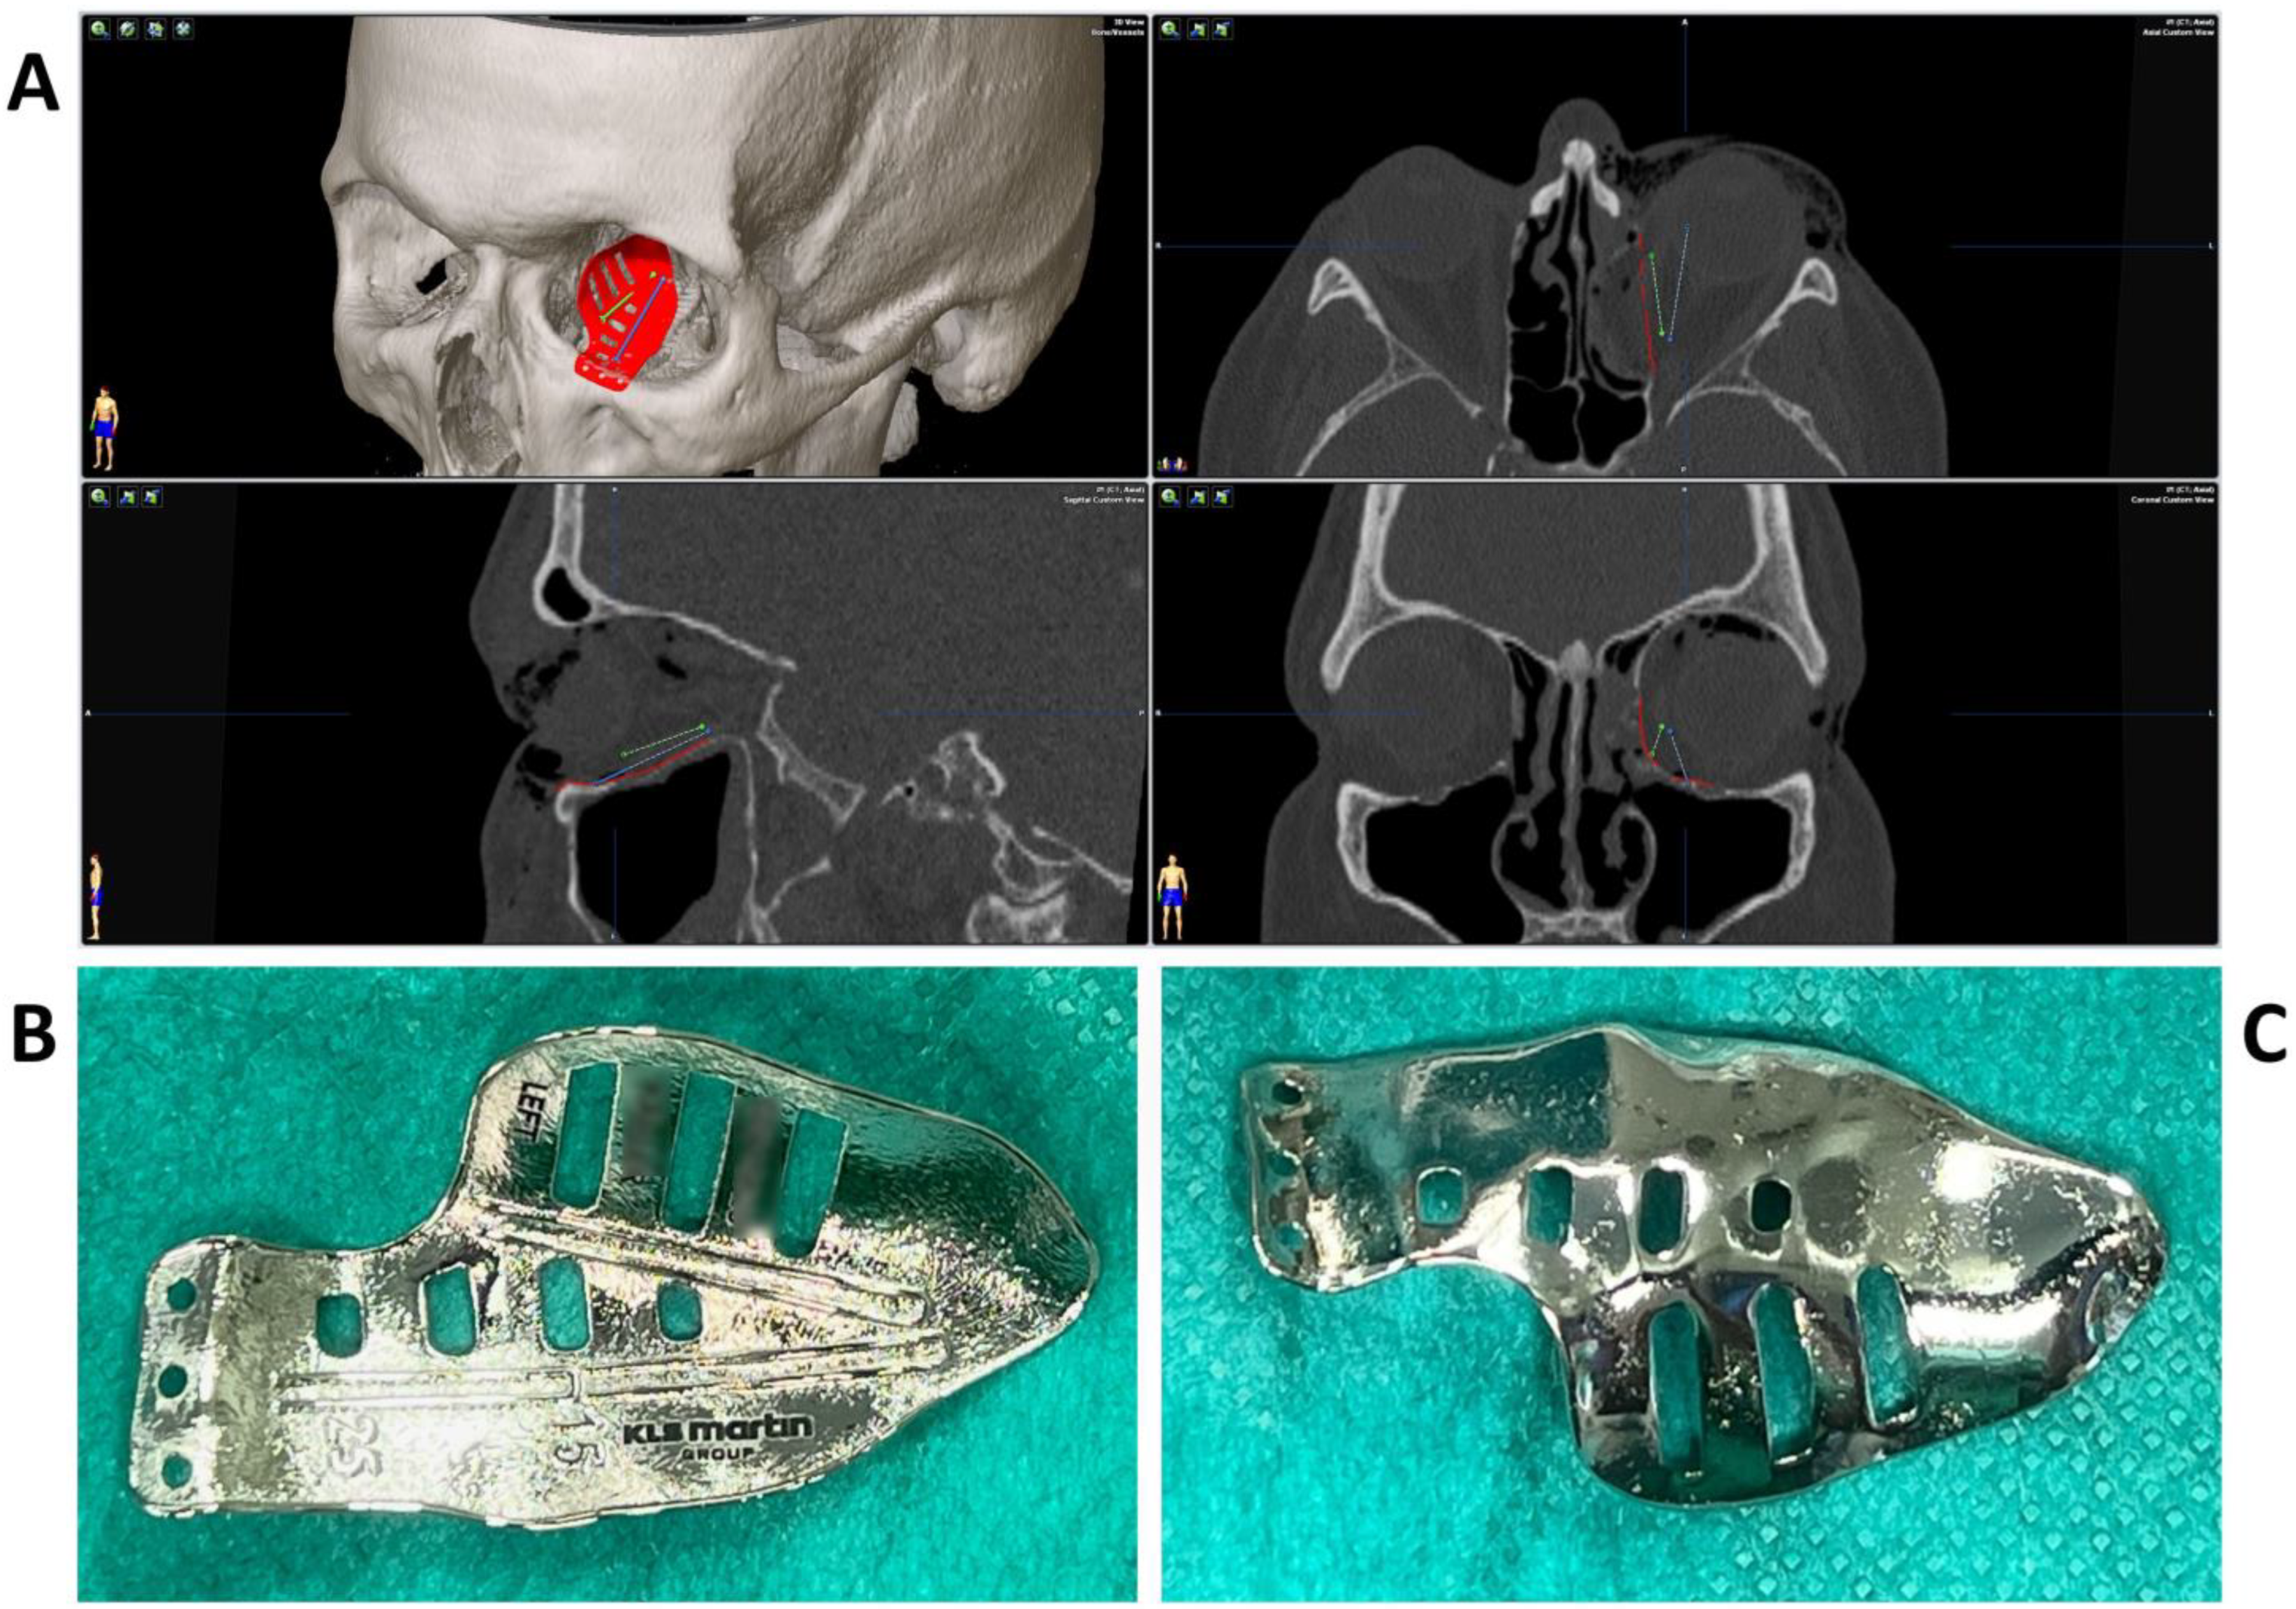

2. Methods and Results

2.2. Surgery